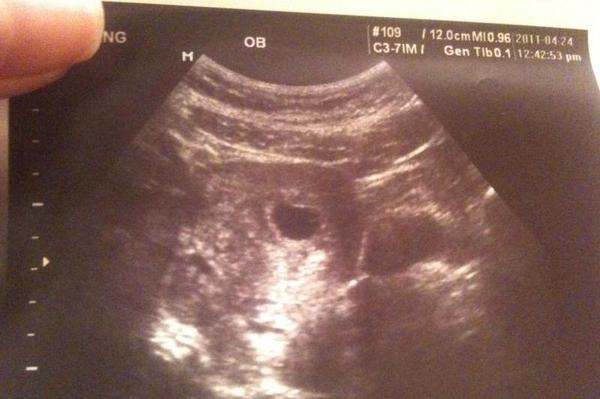

1胎囊的大小:怀孕6周时胎囊直径约2厘米,孕10周时约5厘米,孕15个月时直径约2厘米,25个月时约5厘米为正常。 2胚囊:(长)23*(宽)17*(厚)16 mm 是女孩。或35*34*28mm也是女孩。或18*16*8mm也是女孩。33*18mm是男孩,44*mm是男孩。 350D的BC数据:胎囊29*19 mm是男孩。32*mm是女孩。孕囊35*27mm是女孩。 48W的BC 懷孕胎囊的轉變 1、4周, 胎寶寶僅有2mm。 精卵結合剛進行胚胎著床, 羊膜腔才產生, 容積不大。 超聲波還看不清楚懷孕征兆。 2、5周, 胎寶寶長到4mm, 進入了試管胚胎期, 羊膜腔擴張, 初始心腦血管病出現, 可有心搏。 B超可看到小孕囊, 孕囊約占宮腔內不上1/4, 或由此可見胎

4周胎囊-孕囊 4周 02cm 5周 04cm B超孕囊占宫腔不到1/4 6周 085cm B超胎囊清晰可见 7周 133cm 胎囊约占宫腔的l/3 8周 166cm B超可见胎囊约占官腔1/2 9周 215cm B超可见胎囊几乎占满宫腔 10周 2cm 超可见胎囊开始消失 11周 362cm B超可见胎囊完全消失 一般孕周和孕囊大小不用孕妈妈本人进行纠结比较 胎芽一般是在怀孕三十多天以后开始慢慢形成的,通常妊娠三周至妊娠第一个月称为胎芽期,一般孕6—7周B超可见胎芽,大小在051cm左右,胎芽和孕囊大小的对照关系如下: 怀孕周数 孕囊大小 胎芽 4周 孕囊03cm 孕囊体积很小,超声还看不清妊娠迹象 5周

怀孕4周时,受精卵才着床成功; 怀孕5周时,受精卵着床成功后一边快速进行细胞分裂,一边向四周扩展,而这些细胞将会形成羊膜和血管包裹住 卵黄囊,胎儿就是从卵黄囊开始发育的。 在卵黄囊的外面是孕囊,孕囊是原始的胎盘组织。 所以, 一般在怀孕56周,可以做B超看到孕囊和卵黄囊,月经规律的女性,最早在怀孕35天时可以通过阴超看到孕囊; 怀孕67周时,可以通过B超看到胎3 怀孕5周孕囊大小多少是正常的 1、4周:胎儿只有02厘米。 受精卵刚完成着床,羊膜腔才形成,体积很小。 超声还看不清妊娠迹象。 2、5周:胎儿长到04厘米,进入了胚胎期,羊膜腔扩大,原始心血管出现,可有搏动。 B超可看见小胎囊,胎囊约占宫腔不到1胎芽特征 怀孕的第一个月为胎芽期,新生命在此期的成长速度是其一生中最快的。 妊娠第二周末精卵结合,受精后约4天,分裂成细胞团的精卵沿着 输卵管 到达子宫。 第三周,细胞团脱去外膜,为着床作准备。 第四周,胚泡已牢固地植入子宫里。 在这个